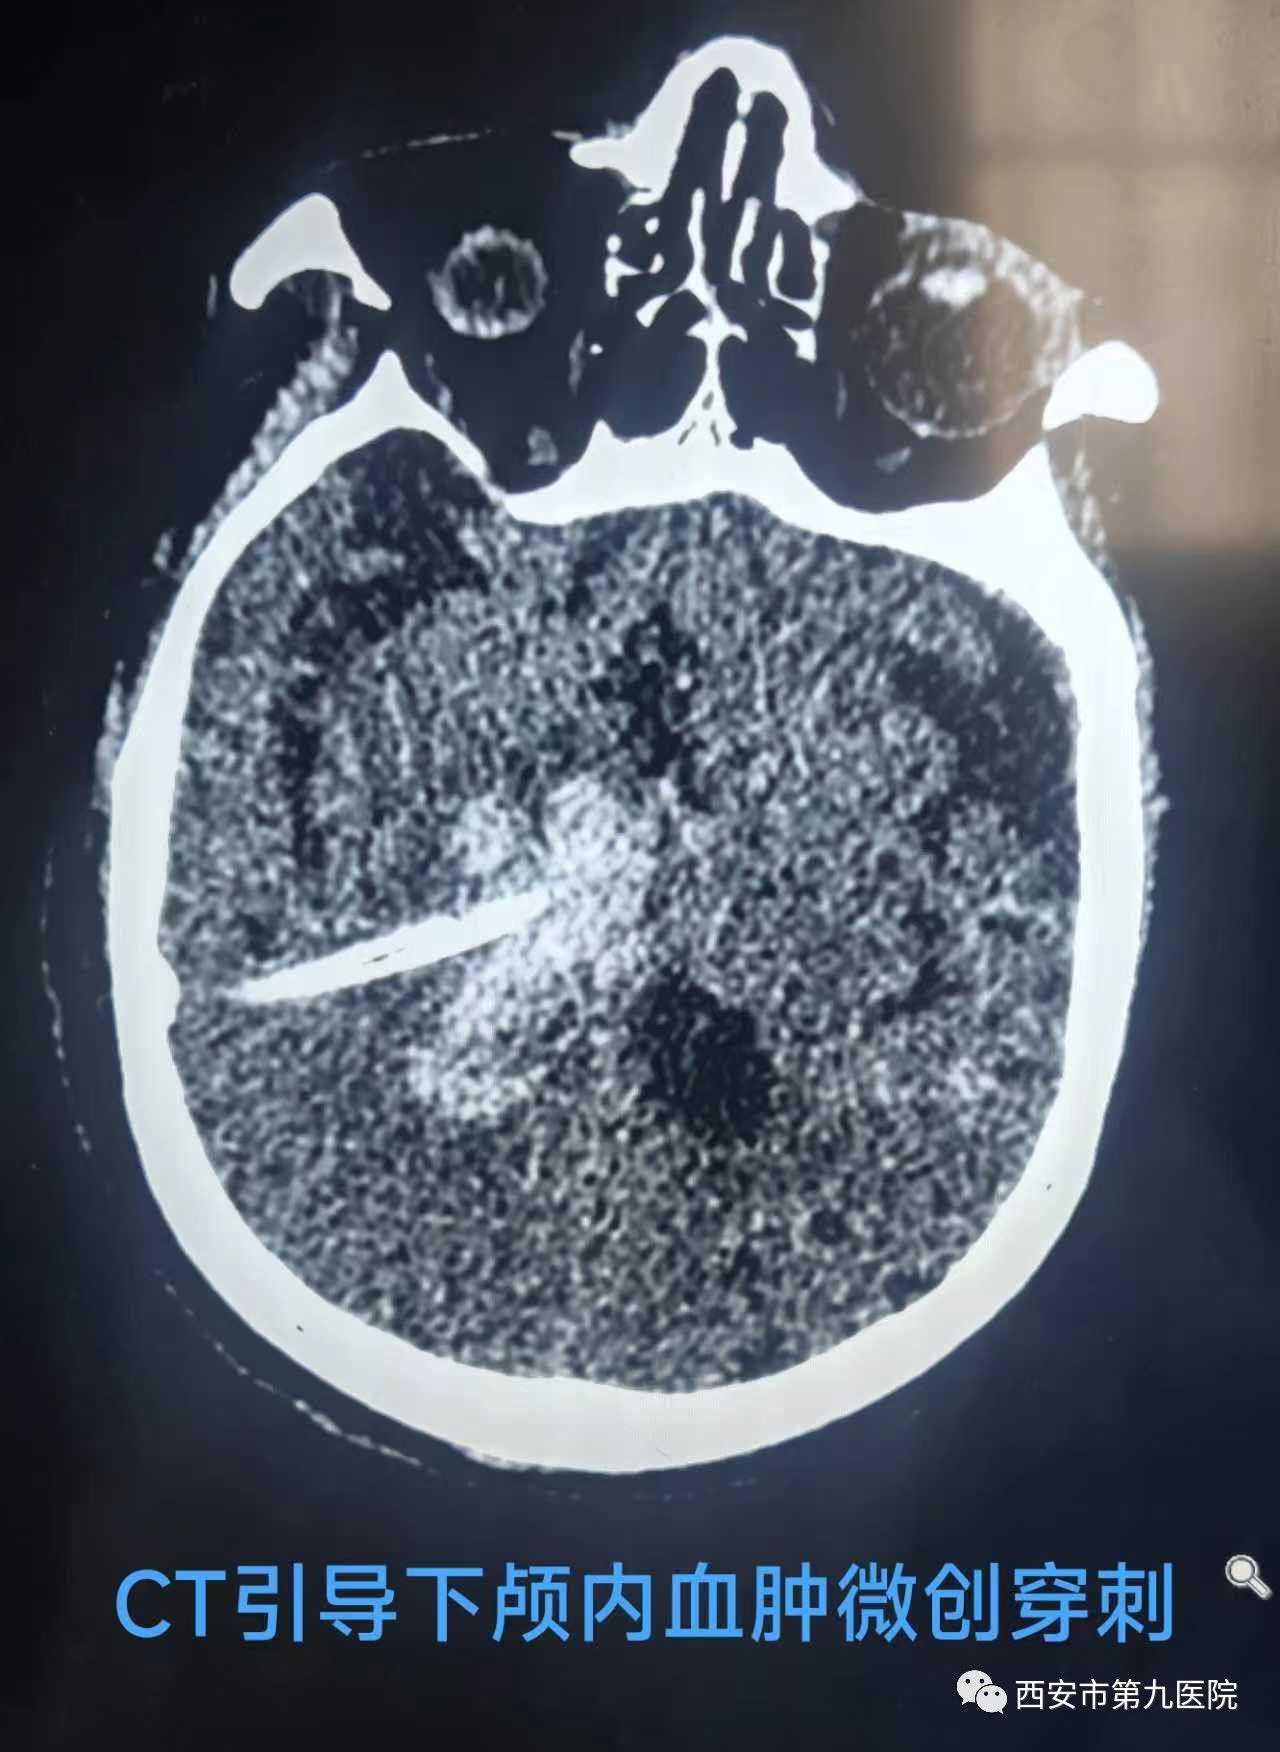

患者赵某,80岁,因意识丧失3小时就诊于西安市第九医院,急诊行CT检查,见右侧基底节区高密度影,考虑脑出血,因为出血在CT上看也是白色,所以我们可以叫它“白脑”,因患者年龄大,出血量多,急诊科第一时间邀请九院神经外科急会诊,刘晓勇主任医师接诊患者,详细了解病情后,为了减轻患者的损伤,决定急诊行CT引导下微创脑内血肿清除术。

微创手术相比传统手术有创伤小,时间短,术后恢复快等优点,但也提出更高的要求,因为无法像传统开颅手术一样可以直视出血点,一旦术中出血将对病人造成更大的伤害,不过九院神经外科开展的CT引导下微创脑内血肿清除术可以在术中由CT实时定位,不但可以最大程度的避免损伤其他血管,还可以精准定位出血部位,更有效的清除血肿。刘晓勇主任医师带领蒋帅、赵英男医师、经过1个小时紧张的手术,老人脑袋里致命的血肿被清除了大半,少量残余血肿也在三天内由引流管引出,老人暂时转危为安。